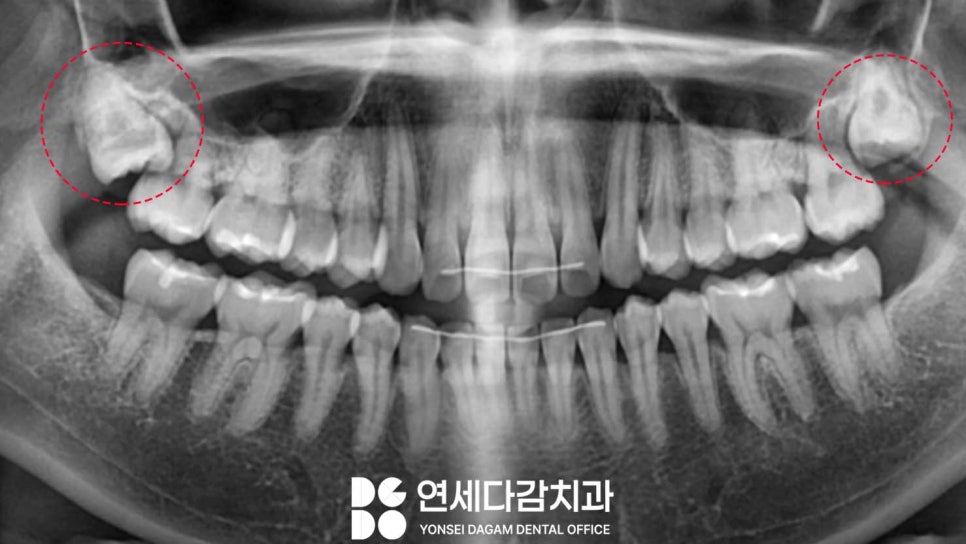

다른 케이스를 살펴보면

심하게 근심으로 기울어져 있는 곳

(사진 기준 왼쪽)과 아닌 곳이 있습니다.

근심으로 기울어져 있는 곳은

개롱역 치과 에서 위에서

언급한 과정대로 진행하게 됩니다.

기울기가 심하지 않은 상악 매복 사랑니는

하악에 비해 더 단순한 과정이

될 수 있습니다.

상악골은 하악골에 비해

골밀도가 낮고

해면골의 비율이 높아

발치가 상대적으로 용이합니다.